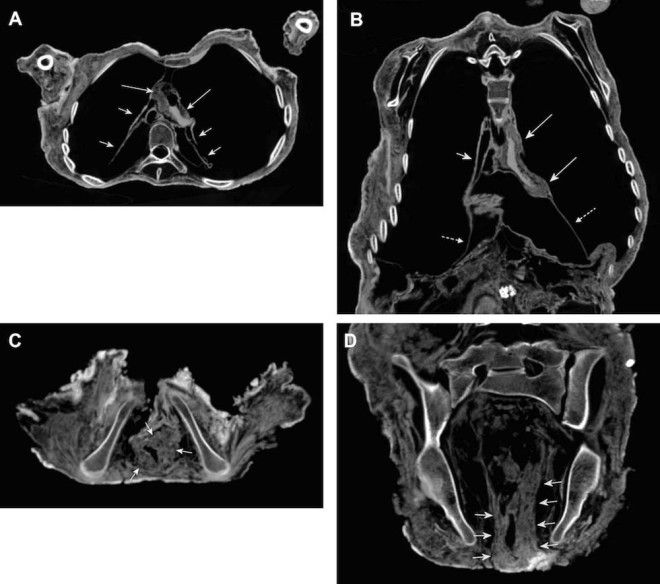

16. Снимки также показали признаки уплотненной стенки сердца и раздутый кишечник. Скорее всего, это было вызвано болезнью Шагаса.

17. Рентгеновские снимки тела инкской мумии.